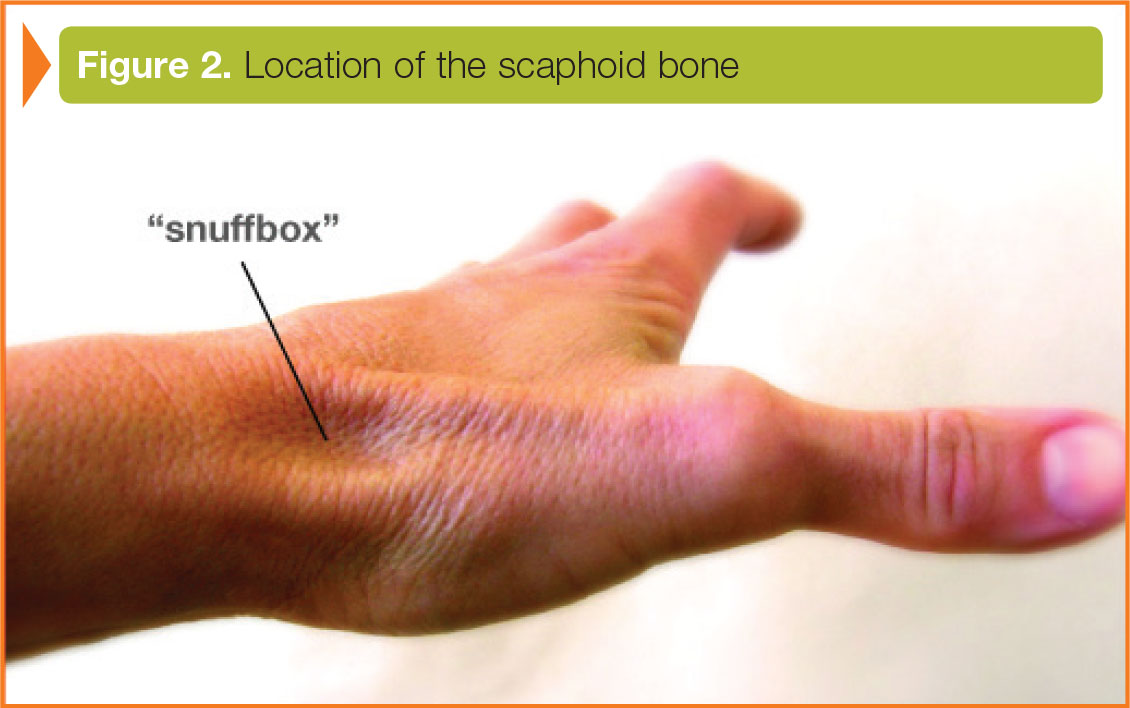

The ligaments of the wrist are external to the wrist and internal to the wrist. The scaphoid has a particularly poor blood supply and gaining healing of this bone can be difficult-complications with treatment and healing are common. Treatment of these fractures spans from nonoperative treatment in a cast or brace to surgical management. These injuries often masquerade as wrist sprains-and initial radiographs may not reveal the fracture. These fractures are often associated with tenderness on the top of the wrist. The scaphoid (navicular) is one of the proximal carpal bones and may be injured in a fall. If a fracture is present, it will usually be apparent on repeat films because of reabsorption of bone along the fracture site.A Patient’s Guide to Scaphoid (Navicular) Fracture with Animated Surgical Video Introduction These patients should be placed in a thumb spica cast for 2 weeks and return for repeat radiography. Occasionally, patients can present with snuffbox tenderness after a fall on an outstretched hand, and will have no radiographic abnormalities. The third radiograph shows a very subtle fracture appearing as a fine, irregular lucency through the waist. The second radiograph shows a fracture appearing as an irregular lucent line through the waist of the scaphoid. The first radiograph below shows a fractured scaphoid appearing as a small break in the cortex. With healing, there is reabsorption of bone along the fracture line, making it more visible at 2 weeks.įractures of the scaphoid bone can be very subtle and even missed on the initial radiograph. If a patient has tenderness in the area of the anatomic snuffbox, but no fracture is apparent on x-ray, he/she should be immobilized in a thumb spica cast and instructed to return for repeat x-rays in 2 weeks. These can lead to chronic pain and instability of the wrist. Failure to recognize and appropriately manage these fractures can result in avascular necrosis of the scaphoid bone and/or non-union of the fracture. If displaced, they require urgent orthopedic consultation for reduction. If undisplaced, these fractures are managed with a thumb spica cast which immobilizes the wrist and the thumb. The scaphoid bone is the most commonly fractured carpal bone, accounting for 50-60% of all carpal injuries. Note on the oblique radiograph that there is a lucent line representing a fracture through the waist of the scaphoid bone. There was considerable swelling and tenderness in the anatomic snuffbox. This 35 year old female patient fell from her bike and suffered a hyperextension of her wrist.